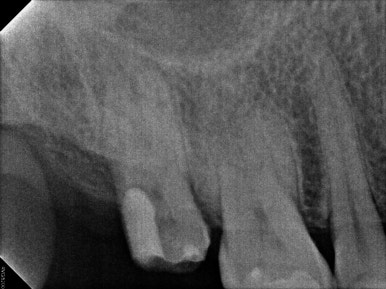

좌: 신경치료 전, 우: 신경치료 후

가장 먼저 증상이 있어 불편해하셨던 오른쪽 위 어금니 (17번 치아) 신경치료부터 마무리 하였습니다.

어금니 신경치료는 생각보다 상당히 어려운 치료입니다. 그러기에 반드시 '치과보존과 전문의'가 있는 치과에 방문하시라고 꼭 일러드리고 싶어요.

치아 내부에 있는 신경을 깔끔하게 제거하고 소독한 뒤 알맞게 재료로 잘 채워넣은 것을 보실 수 있을겁니다.

또한 충치로 비어있던 자리는 레진 코어로 완료.